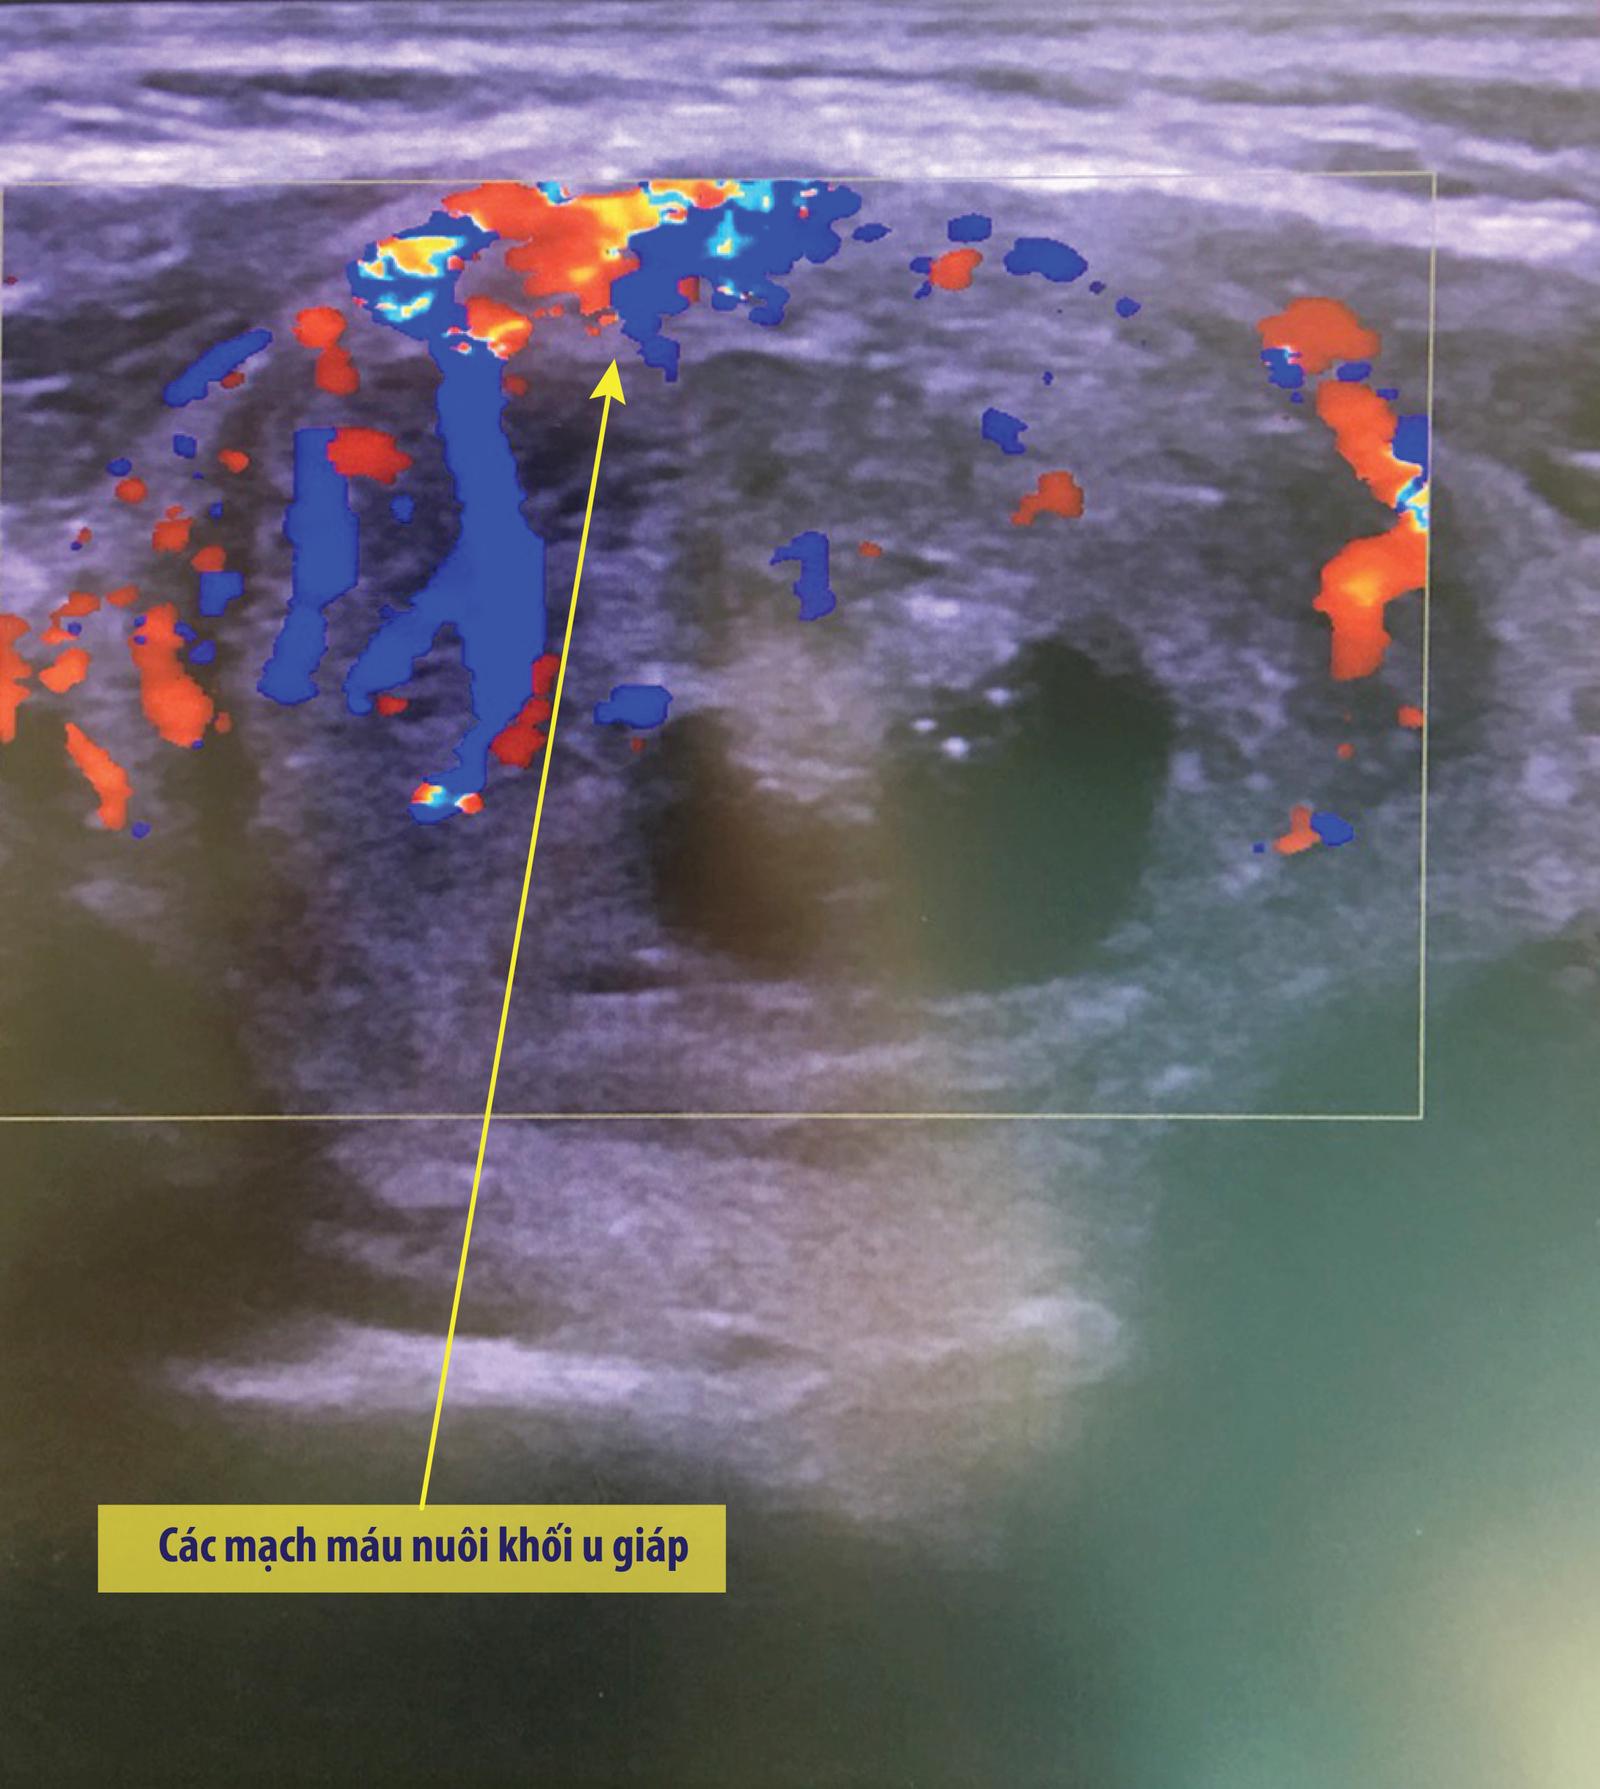

Hình ảnh khối u của bệnh nhân trước và sau khi điều trị

Sau 1 tháng điều trị, thể tích khối u tuyến giáp của chị Na giảm 40%. Hình ảnh siêu âm màu cho thấy không còn mạch máu trong khối u. “Toàn bộ khối lồi ở cổ tôi phải nhìn kỹ mới phát hiện ra, không lộ như trước. Tôi cũng không còn đau cổ nữa, đặc biệt rất ưng ý vì không có sẹo” – chị Na cho biết.

Hình ảnh khối u giáp sau khi đốt sóng cao tần không còn mạch máu nuôi u